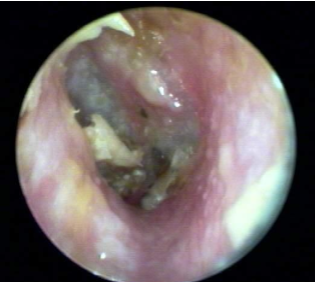

Otomycosis

Fungal ear infection of the EAC. Common in hot and humid areas.